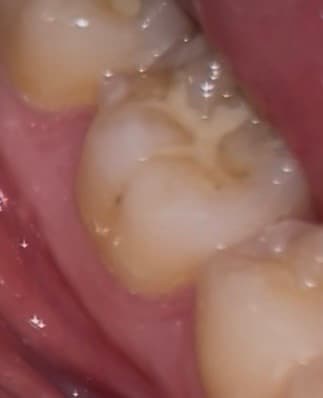

이정도 치아 깨진거 치료 받아야할까요? +충치

딱딱한거 씹다가 깨졌는데

가끔 뜨거운거 먹었을때시큰거리는 정도고

일상생활할때 불편한건 없습니다

• 1번 째 사진

사진으로 봤을 경우에 치아가 깨진 것보다 부분 부분 충치가 보이고 있습니다. 충치가 있는 부분엔 이물질이 남아 있게 되어 충치가 진행될 수 있으니 충치가 있는 부분은 치료를 해주는 것이 좋습니다.

깨진 정도가 크진 않으나 한번 깨졌던 치아는 그 부위가 씹을때 힘이 강하게 가해진다는 것이므로 또 추가적으로 깨질 우려가 큽니다. 전반적으로 상태 보고 레진으로 떼우거나 아니면 크라운을 씌워주면 좋을 것 같습니다.